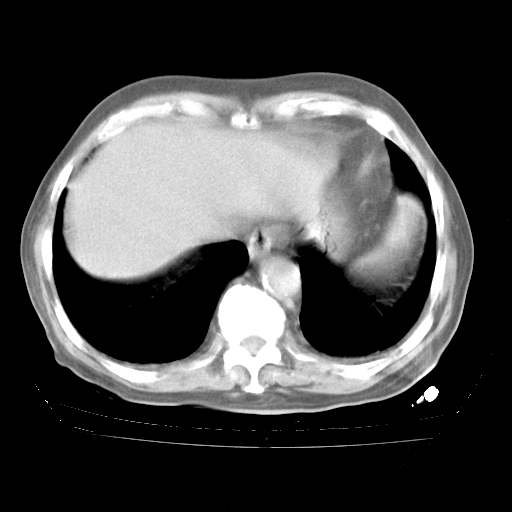

4月28日肺部CT